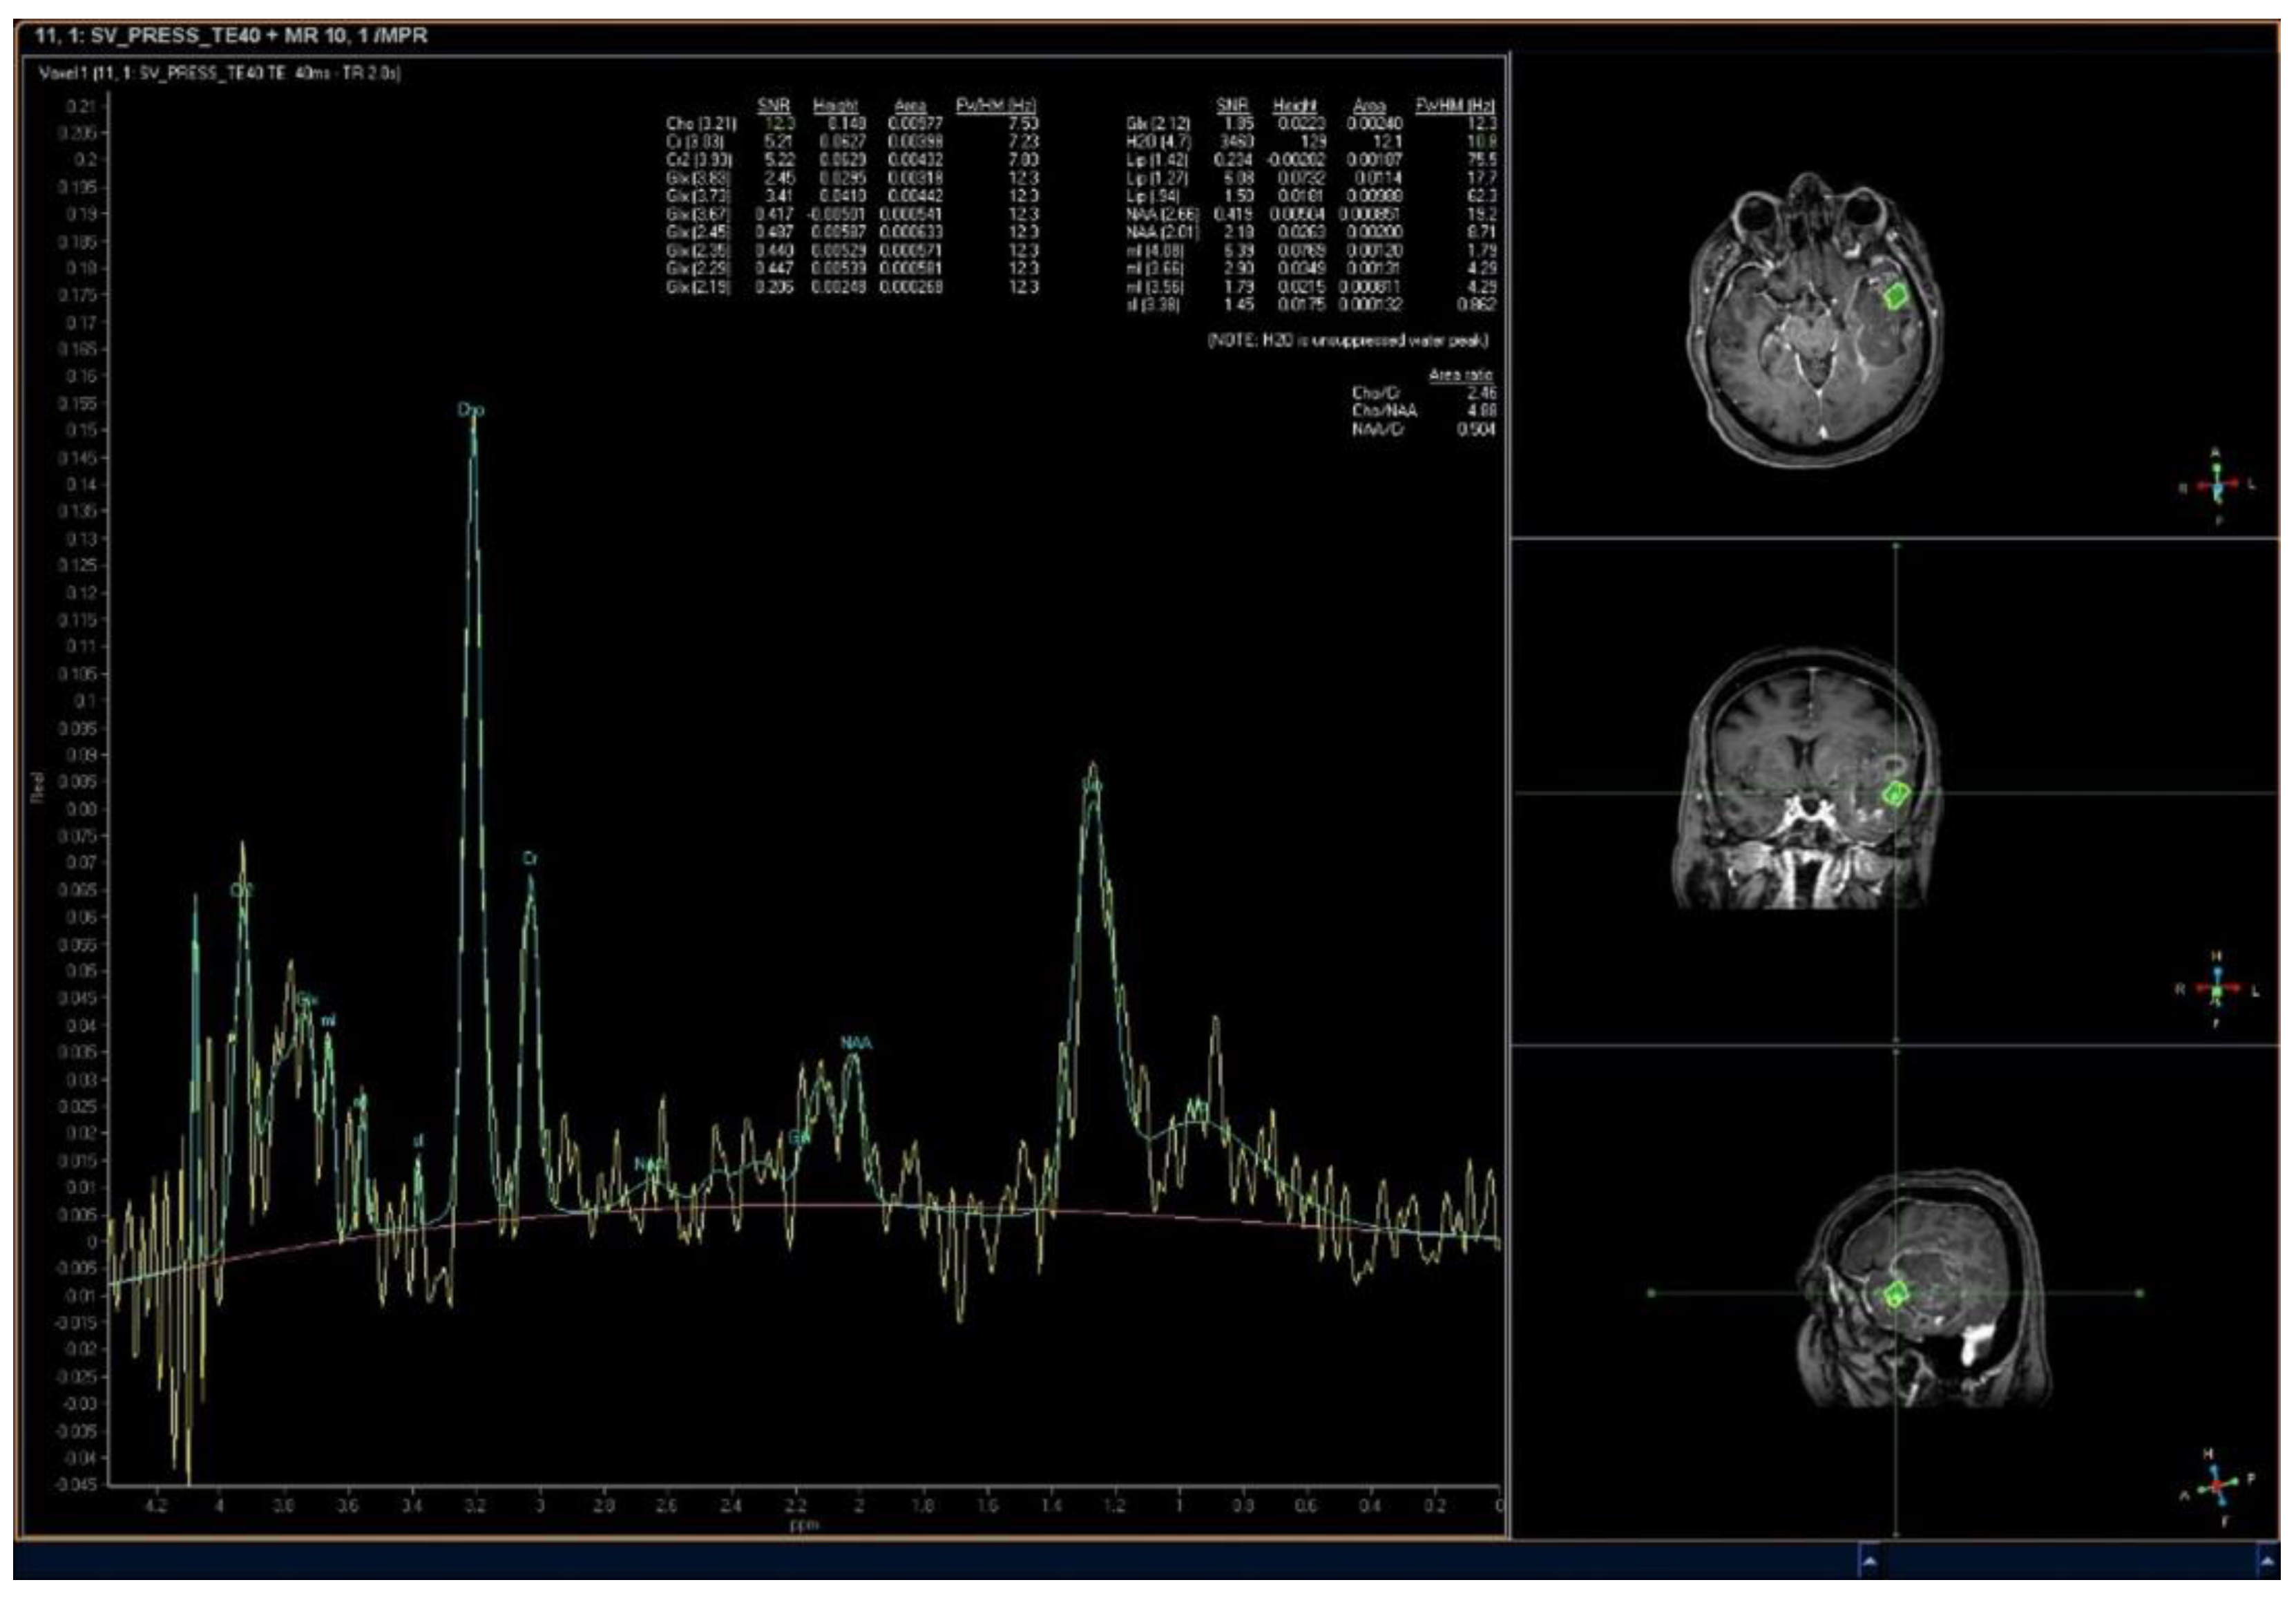

2.7. MR Spectroscopy

3.1. Glioma Grade Classification

3.2. Correlation with Glioma Molecular Profile

- Guo, J.; Yao, C.; Chen, H.; Zhuang, D.; Tang, W.; Ren, G.; Wang, Y.; Wu, J.; Huang, F.; Zhou, L. The relationship between Cho/NAA and glioma metabolism: Implementation for margin delineation of cerebral gliomas. Acta Neurochir. 2012, 154, 1361–1370. [Google Scholar] [CrossRef]

- Croteau, D.; Scarpace, L.; Hearshen, D.; Gutierrez, J.; Fisher, J.L.; Rock, J.P.; Mikkelsen, T. Correlation between Magnetic Resonance Spectroscopy Imaging and Image-guided Biopsies: Semiquantitative and Qualitative Histopathological Analyses of Patients with Untreated Glioma. Neurosurgery 2001, 49, 823–829. [Google Scholar] [CrossRef]

- Kumon, M.; Nakae, S.; Murayama, K.; Kato, T.; Ohba, S.; Inamasu, J.; Yamada, S.; Abe, M.; Sasaki, H.; Ohno, Y.; et al. Myoinositol to Total Choline Ratio in Glioblastomas as a Potential Prognostic Factor in Preoperative Magnetic Resonance Spectroscopy. Neurol. Med.-Chir. 2021, 61, 453–460. [Google Scholar] [CrossRef]